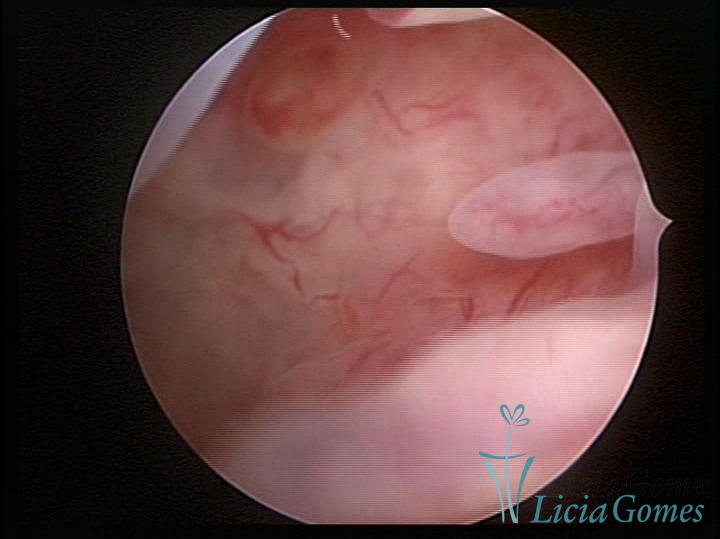

Este pode apresentar uma gama variável de aspectos macroscópicos, com aspecto pseudopolipoide; lembrando tecido cerebroide ou com reação deciduoide;a vascularização superficial é mais evidente e com vasos em formatos de saca-rolha ou espirais visualizando também a vascularização com atípias, com aumento do calibre dos vasos superficiais, pode ser encontrado também tecido em necrose, poderá haver um pequenos dendritos (papilomatoso).